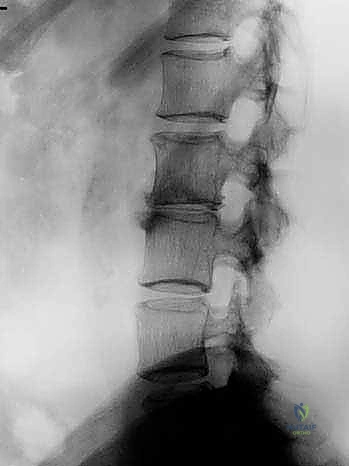

- الأشعة السينية الديناميكية (Dynamic X-rays): صور في وضعيات الانحناء للأمام والخلف لتقييم مدى عدم استقرار العمود الفقري (الانزلاق الفقري - Spondylolisthesis).

الخطوة 5: التثبيت (Fixation)

لضمان أقصى درجات الثبات والسماح للعظم بالاندماج بمرور الوقت، يتم تثبيت القفص باستخدام شريحة معدنية صغيرة ومسامير من التيتانيوم تُثبت في الأجسام الفقرية من الأمام. في بعض الحالات، قد يرى الدكتور هطيف ضرورة إضافة تثبيت خلفي بمسامير عبر الجلد (Percutaneous Pedicle Screws) لزيادة الدعم.

الخطوة 6: الإغلاق

بعد التأكد من وضعية الغرسات باستخدام الأشعة السينية داخل غرفة العمليات، يتم إعادة الأوعية الدموية والأعضاء الداخلية إلى وضعها الطبيعي، وتُغلق طبقات البطن بخيوط تجميلية.